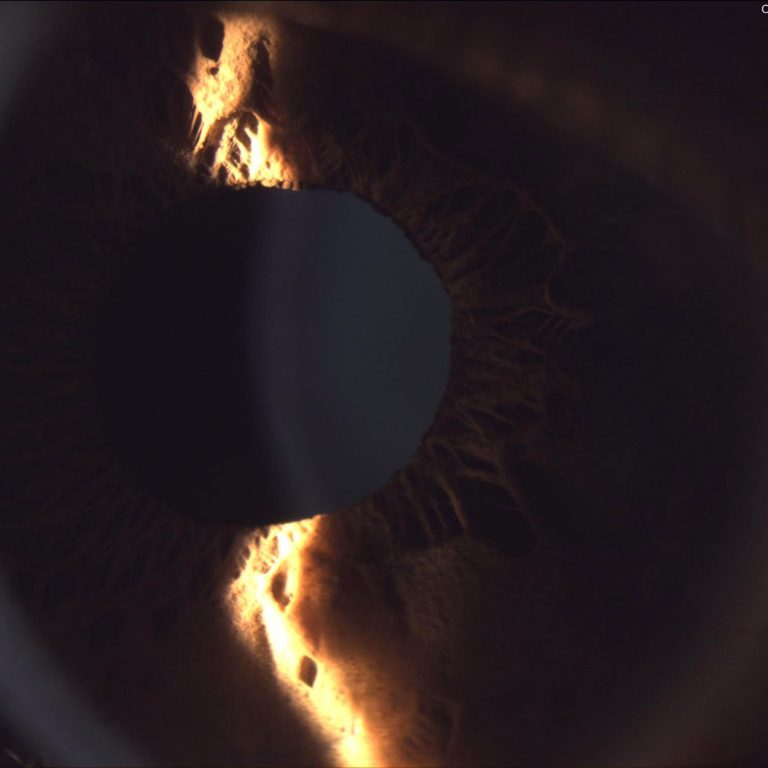

Spaltlampenuntersuchung

Mit der Spaltlampe lassen sich Augenoberfläche, Hornhaut, Linse, Netzhaut und weitere Strukturen des Auges stark vergrößert betrachten. So können selbst kleinste Veränderungen frühzeitig erkannt und die Augengesundheit umfassend beurteilt werden.

Ihr Auge ganz groß am Bildschirm

Mir ist transparente und verständliche Kommunikation besonders wichtig.

Mit Hilfe moderner Bildgebung zeige ich Ihnen Aufnahmen Ihrer Augen direkt am Bildschirm und erkläre Ihnen anschaulich, was ich sehe.

Auf Wunsch erhalten Sie die Bilder auch digital -sowohl zur Weitergabe an Ihre Augenärztin oder Ihren Augenarzt als auch für sich persönlich, als beeindruckende Großaufnahme Ihres Auges.